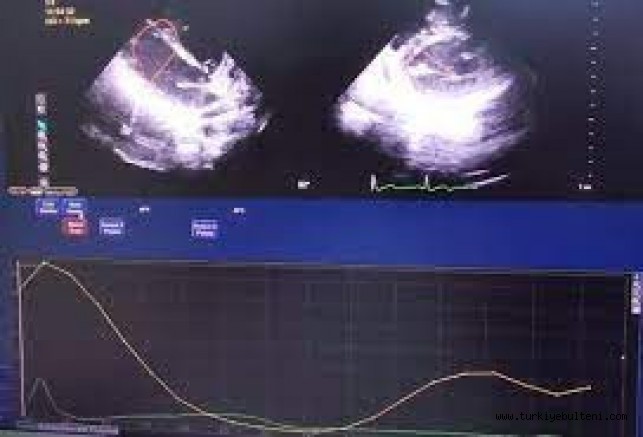

Ordu Üniversitesi Eğitim ve Araştırma Hastanesi Dahili Tıp Bilimleri Bölümü Kardiyoloji Ana Bilim Dalı öğretim üyeleri Doç. Dr. Osman Bektaş ve Dr. Fatih Akkaya tarafından ‘Sağ ventrikül üzerinde hafif şiddette Covid-19'un uzun vadeli etkileri’ başlıklı çalışma gerçekleştirildi. Çalışmada, 3 ay boyunca Covid-19 testi pozitif çıkan ve ayakta tedavi edilen 105 hasta ve sağlıklı 105 kişinin kalp atış hareketleri izlendi. Kişilerin ventrikül fonksiyonları konvansiyonel 2 boyutlu ekokardiyografi ve 2D ileri ekokardiyografik sistemi ile görüntülendi. Araştırmada, koronavirüse yakalananlarda kalp yetmezliğine yol açan kalp kasılma fonksiyonu düşüklüğü belirlendi.

Çalışmayla ilgili bilgi veren Doç. Dr. Osman Bektaş, koronavirüsü hafif geçirenlerde de etkilenme olduğunun belirlendiğini söyleyerek, “Covid-19 pandemisinden itibaren oldukça uzun süre geçti. Bizim de Covid hastaları üzerindeki tecrübemiz arttı. Bu çalışmada Covid polikliniğine gelen ve yatış gerektirmeyen hastalar üzerinde çalıştık. Özellikle testleri pozitif olan hastalar üzerinde kalp ultrasonu ile değerlendirme yaptık. Çalışmada özellikle ayakta Covid-19 geçiren hastalarda yani yatış gerektirmeyen hastalarda bile etkilenmelerin olduğunu tespit ettik. Yaptığımız çalışmalarda özellikle kalbin sağ tarafının etkilendiğini belirledik” diye konuştu.

Koronavirüs hastalarının bazılarında kalp enzimlerinin yüksek seyrettiğini de kaydeden Doç. Dr. Bektaş, “Kalp kasılma kusuru olmayan ancak Covid geçirdikten sonra kalp yetersizliği olan birçok hasta gördük. Temelde salgını ayakta bile geçirse kardiyak etkilerinin olduğu görülüyor. Burada yatış gerektiren hastalarda kalp kası etkilenmesi ve iltihaplanması Covid hastalarında zaten oluyordu ama ayakta hastalığı geçirenlerde etkilenme oluyor mu, diye baktık. Bu özel görüntülemede strain dediğimiz kasılma kusuru olup olmadığını değerlendirdik. Bu çalışmada klinik verilerin, koronavirüs hastalarında özellikle kalp enzimlerinde yükselmeyle beraber seyrettiği görülüyor. Özetle bir etkilenme olduğunu söyleyebiliriz” dedi.